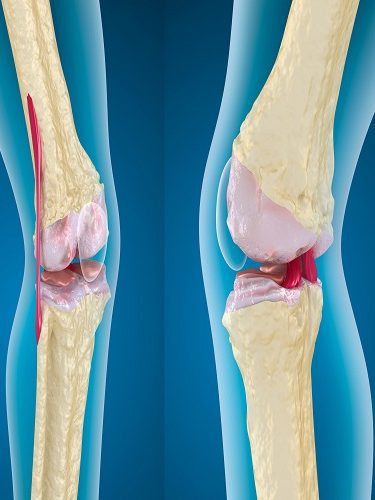

– OVER KİST AMELİYATI (YUMURTALIK KİSTİ AMELİYATI) (OVER KİSTEKTOMİ) Hemen her kadında hayatını belirli bir döneminde over kistlere rastlanabilmektedir. Bu kistlerin farklı tüpleri bulunmaktadır. Bu çeşitliliğe uygun tedavi yöntemleri de bulunmaktadır. Over kistlerinde en sık rastlanan şikayetler cinsel ilişki sırasında ağrı, kasık ağrısı, karında şişkinlik veya basınç hissi ve adet düzensizlikleridir. Yumurtalık (over) kistleri her…